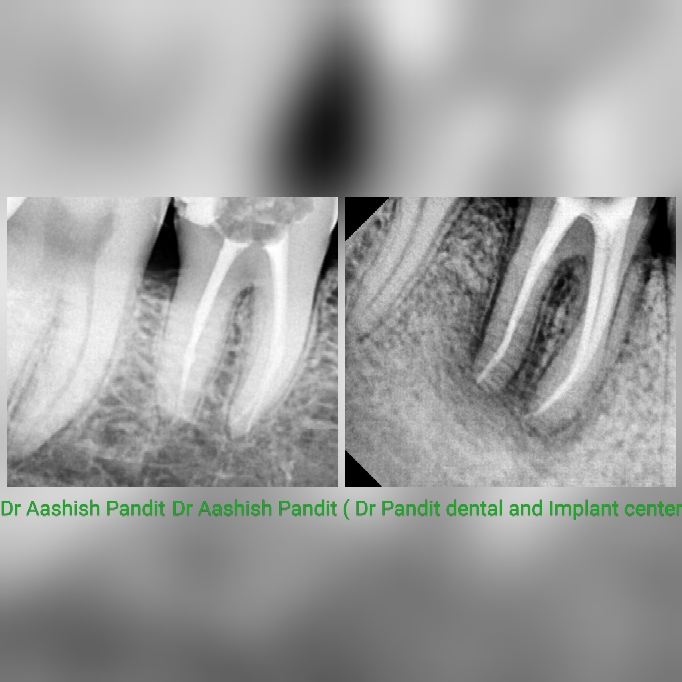

Root canal or endodontic treatment is necessary when the pulp of tooth becomes infected or inflamed. This may be because of various reasons such as deep decay, trauma to the tooth, faulty restoration or crown, cracked or chipped tooth etc. Visit Dr Pandit dental and Implant center for Single visit root canal, dental implants, dentures, bleaching, best dental clinic, Delhi, janakpuri, sagarpur, vashist park. Dr Aashish Pandit, Dr Preeti kaushik.